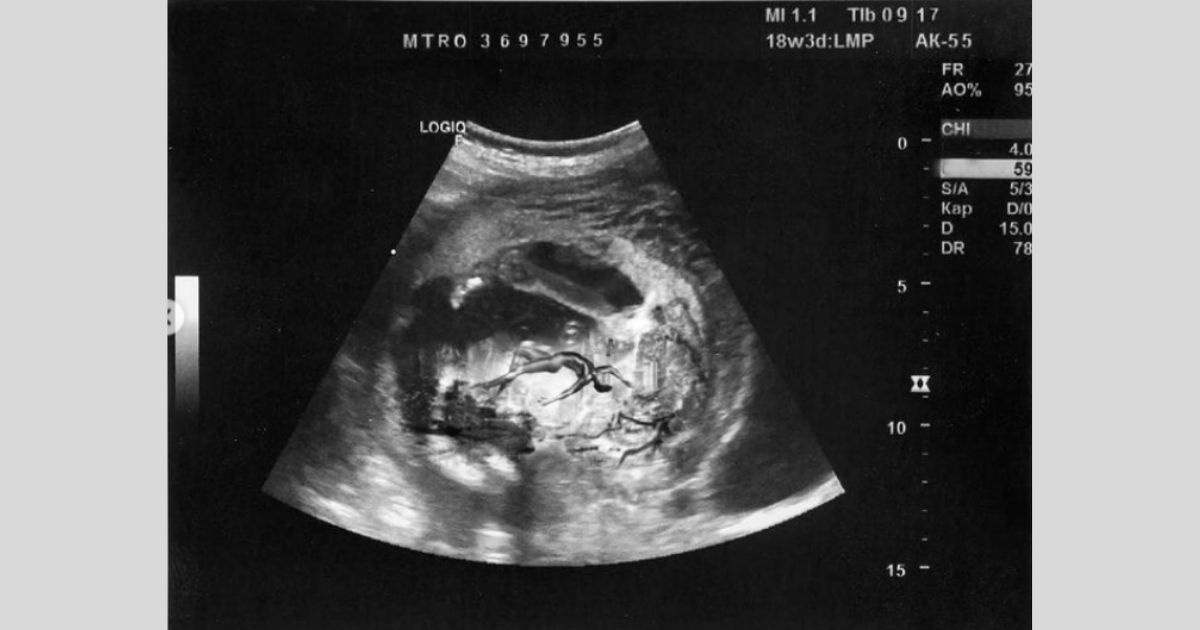

The 22-year-old rapper-musician jokingly said that ‘baby Montero is due September 17, 2021’ as he touches his prosthetic belly while smiling for the camera.